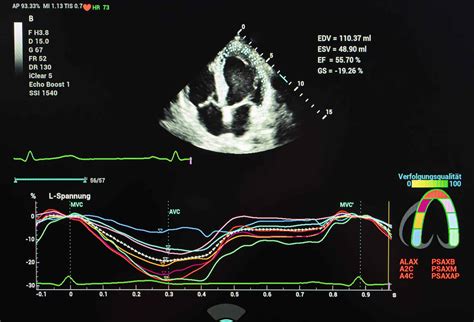

Bei dieser Untersuchung werden hochfrequente Schallwellen verwendet, um detaillierte Bilder des Herzens des Fötus zu erstellen. Die Beurteilung des kindlichen Herzens erfolgt sowohl in der sogenannten B-Mode Sonografie (Schwarz-Weiß-Darstellung) als auch mit Hilfe der Farbdoppler-Sonografie. Hierdurch können die Blutflüsse und Blutflussrichtungen überprüft werden.

Der Hauptzweck der fetalen Echokardiographie besteht darin, das fetale Herz auf strukturelle Anomalien, Rhythmusstörungen oder Durchblutungsstörungen zu untersuchen. Dabei werden folgende Aspekte beurteilt:

- Herzstruktur: Beurteilung der Herzkammern, Vorhöfe, Klappen und großen Gefäße auf Fehlbildungen.

- Herzfunktion: Beurteilung der Pumpfunktion des Herzens und der Koordination der Herzschläge.

- Blutfluss: Überprüfung der Richtung und Geschwindigkeit des Blutflusses durch das Herz und die großen Blutgefäße mittels Doppler-Sonografie.